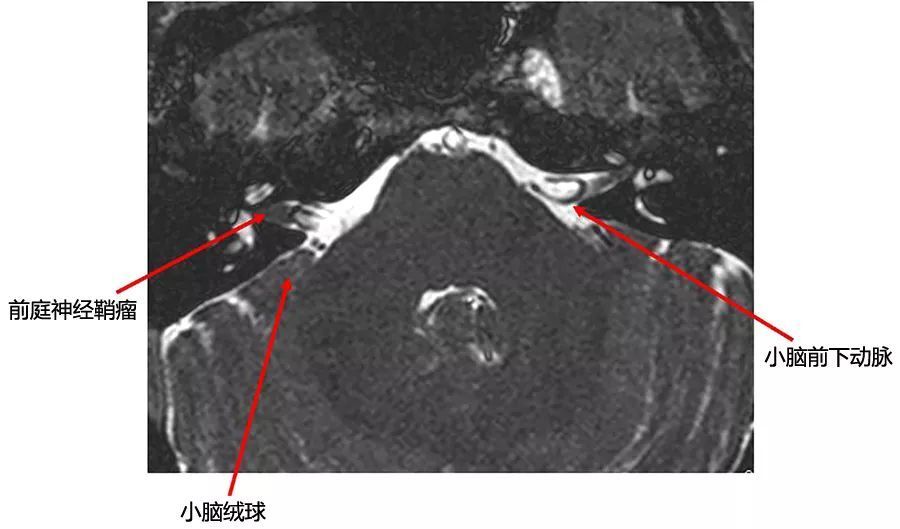

图10  右侧前庭神经鞘瘤。位于内听道基底部,向上延伸至耳蜗孔,病变随访3年以上未进展